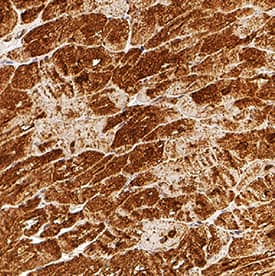

Troponin T antibody in Human Heart by Immunohistochemistry (IHC-P).

Troponin T in Human Heart.

Troponin T was detected in immersion fixed paraffin-embedded sections of human heart using Mouse Anti-Human/Mouse/Rat Troponin T (Cardiac) Monoclonal Antibody (Catalog # MAB18742) at 0.5 µg/mL for 1 hour at room temperature followed by incubation with the Anti-Mouse IgG VisUCyte™ HRP Polymer Antibody (Catalog # VC001). Tissue was stained using DAB (brown) and counterstained with hematoxylin (blue). Specific staining was localized to cytoplasm in cardiomyocytes. View our protocol for IHC Staining with VisUCyte HRP Polymer Detection Reagents.